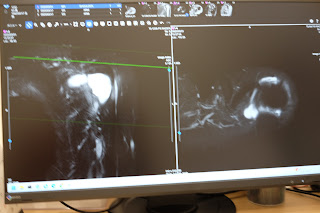

MRI 4/3

結果が出た.

筋肉の挫傷が認められる.

水たまりができている.

しばらくかかるでしょう.

動かせる範囲で動くのがよろしい.

痛みはほとんどないので、明日から日常.